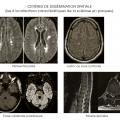

Le diagnostic de sclérose en plaques est fondé sur un faisceau d’arguments cliniques et paracliniques (fig. 5 et 6) de dissémination temporelle et spatiale d’atteinte du système nerveux central en dehors d’une autre maladie évolutive.

La dissémination spatiale des lésions est prouvée par la mise en évidence d’une atteinte de plusieurs zones du système nerveux central, soit à l’anamnèse ou à l’examen clinique, soit à l’IRM.

La dissémination temporelle des lésions se définit comme la succession d’épisodes neurologiques au sein du système nerveux central dans le temps, elle peut être démontrée à l’interrogatoire, à l’examen clinique ou grâce à l’IRM par la mise en évidence de façon contemporaine de lésions se rehaussant par le gadolinium (signant une souffrance du système nerveux central récente) et d’autres pas. La survenue d’une nouvelle lésion IRM sur un nouvel examen permet d’obtenir aussi ce critère de dissémination temporelle. Enfin, plusieurs études ont montré que chez un patient avec premier épisode démyélinisant, la présence de bandes oligoclonales dans la ponction lombaire était un facteur prédictif indépendant de survenue de deuxième épisode démyélinisant. Ainsi, la ponction lombaire peut suppléer l’absence de critère de dissémination temporelle si elle révèle des bandes oligoclonales pour établir le diagnostic positif.

Cette quête de la dissémination spatiale et temporelle est clinique mais aussi obtenue avec l’IRM. Le diagnostic de sclérose en plaques peut donc être établi devant la survenue de deux poussées mais, en cas de poussée unique, le critère de dissémination temporo-spatiale peut être obtenu par l’IRM.

Critères de McDonald (2017)

Des critères diagnostiques de la sclérose en plaques ont été établis (tableau 1). Ces critères peuvent permettre le diagnostic de sclérose en plaques dès la première poussée à condition que les critères de dissémination spatiale et temporelle soient remplis. La dissémination spatiale est définie par la présence d’au moins une lésion T2 dans 2 des 4 localisations considérées comme caracté­ristiques de la sclérose en plaques : juxtacorticale, périventriculaire, infratentorielle, au niveau de la moelle épinière (tableau 2 ; fig. 7).

La dissémination temporelle est prouvée par l’apparition d’une lésion en T2 quel que soit le délai par rapport à l’IRM initiale ou par la présence sur l’IRM initiale à la fois de lésions se rehaussant par le gadolinium (signant une lésion récente) et de lésions ne se rehaussant pas (tableau 3). Cette deuxième possibilité évite d’attendre la deuxième IRM pour poser le diagnostic de sclérose en plaques chez certains patients avec un syndrome clinique isolé (ou premier événement démyélinisant). La réalisation d’une seconde IRM est nécessaire pour confirmer une dissémination temporelle chez les patients ne remplissant pas ce critère sur l’IRM initiale. L’alternative permettant de suppléer le critère de dissémination temporelle, chez les patients n’ayant pas sur l’IRM initiale à la fois des lésions prenant le gadolinium et d’autres pas, est que l’analyse du liquide cérébrospinal révèle des bandes oligoclonales.